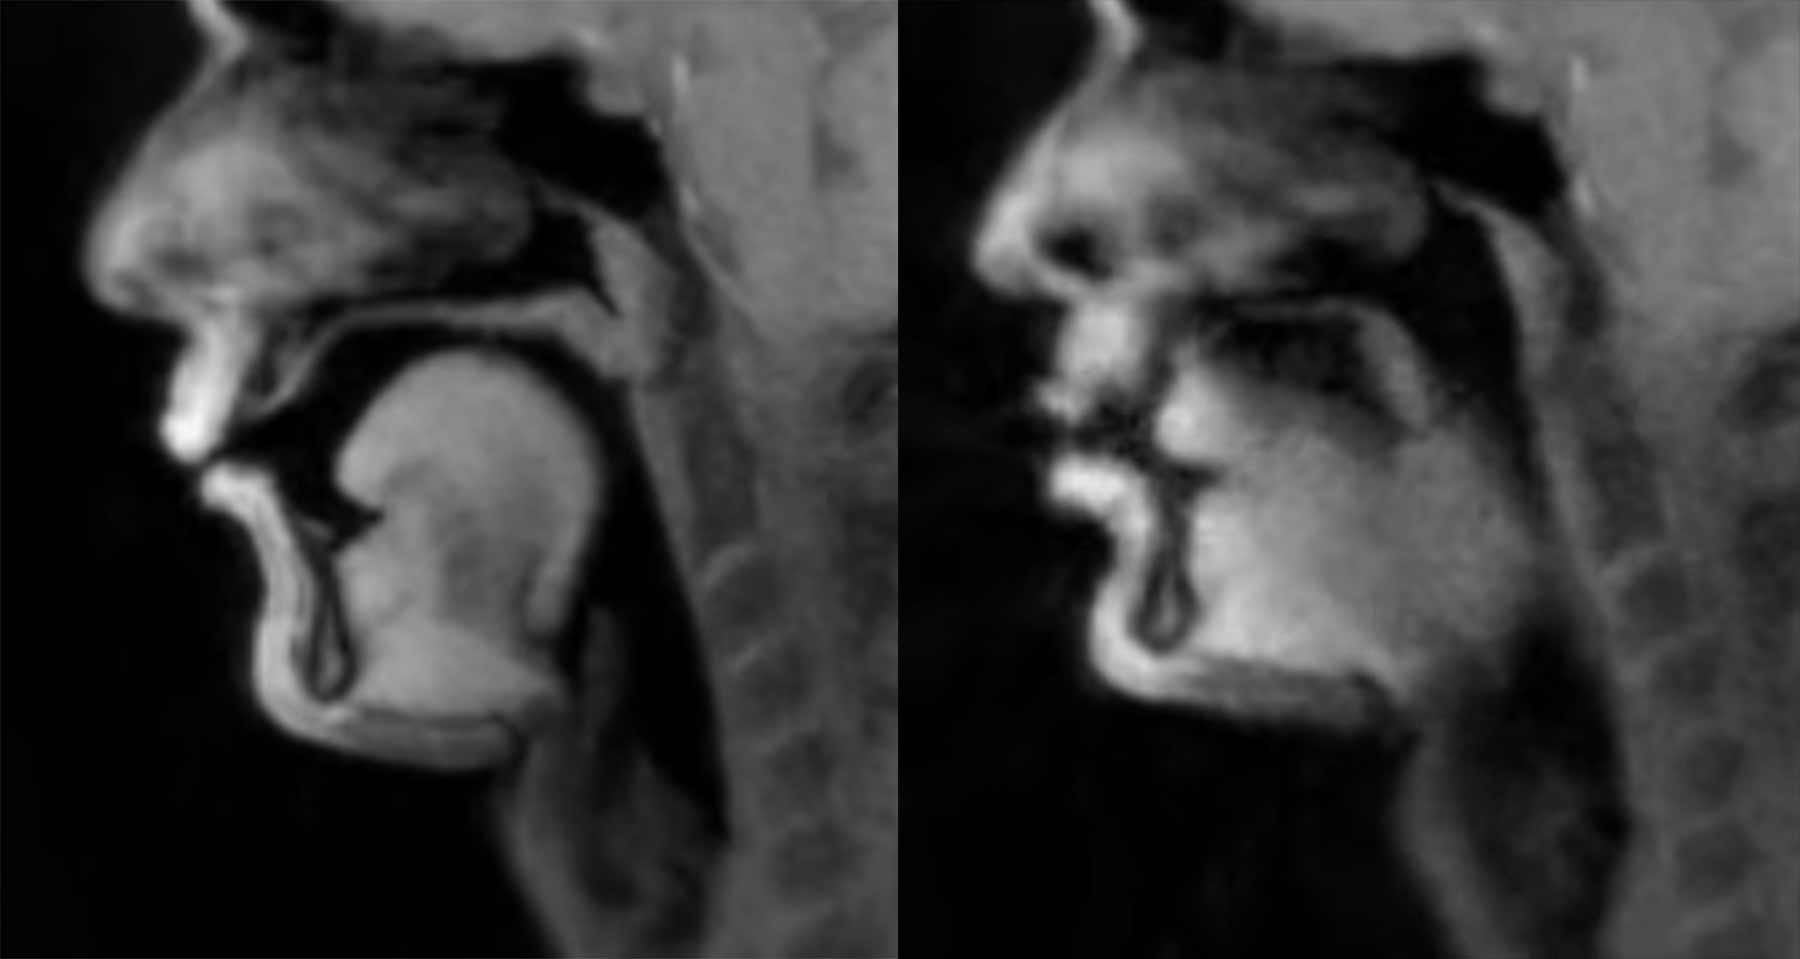

In der WIN Compilation Mai 2018 hatten wir noch einen Ausschnitt, in dem in einem MRT gesprochen wurde. Das war schon ungemein interessant und ein mittelschwerer technisch-medizinischer Durchbruch. Dr. Jens Frahm vom Max-Planck-Institut war das […]